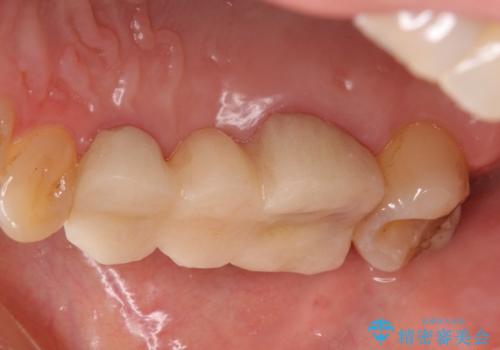

- 他院でブリッジの仮歯を入れたが、外れやすいため転院を希望された患者様です。

支台歯の形が角度が大きくついた形に形成してあり、外れやすい形になっていたため修正してから歯型をとりました。

- 36.3万円(ジルコニアクラウン10万円x3本)費用は治療当時の料金となります

根の治療のやり直しは特に行っていません。